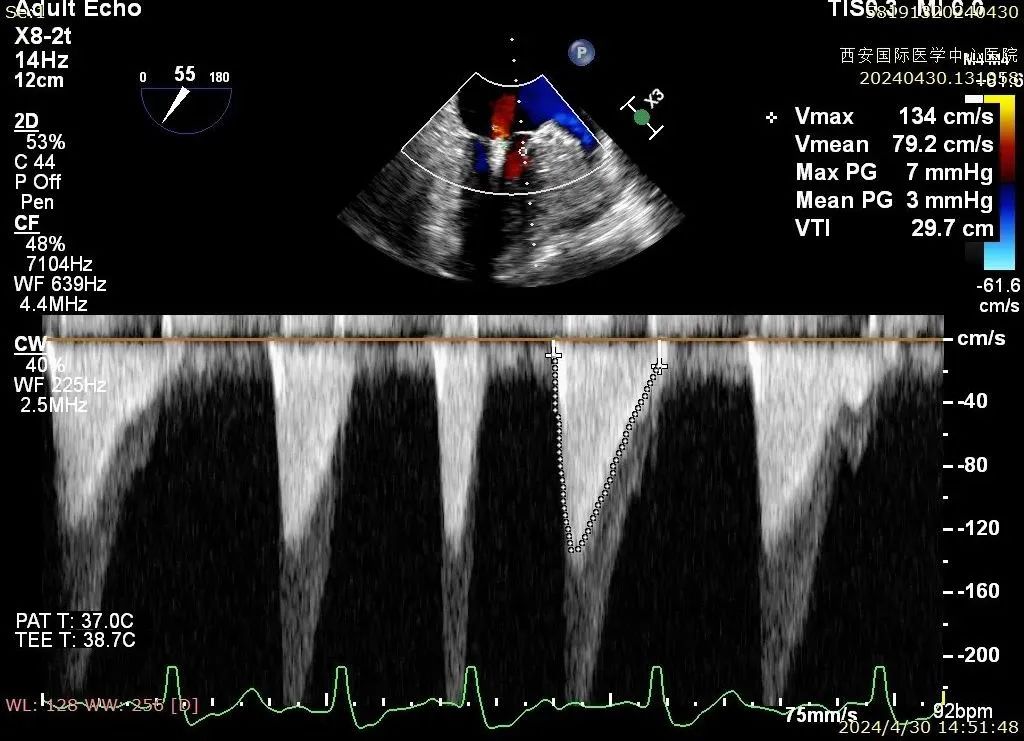

心脏瓣膜介入团队术中在2区植入一枚二尖瓣夹,关闭二尖瓣夹时时刻关注瓣叶张力,并随时释放张力。患者术后反流降至1+,跨瓣压差为3mmHg。

术后二尖瓣反流评估

术后结果